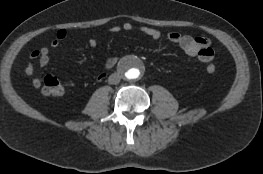

Мультиспиральная компьютерная томография является лучевым методом исследования и в режиме ангиографии применяется для диагностики сосудистой патологии брюшной аорты и ее ветвей. Сканирование проводится с помощью рентгеновских лучей, которые испускает трубка томографа, непрерывно вращаясь вокруг объекта исследования.

Особенностью КТ-ангиографии является обязательное применение контрастного усиления, которое позволяет визуализировать кровеносные сосуды. С помощью внутривенного введения йодсодержащих контрастных препаратов на снимках хорошо контрастируются висцеральные ветви и сама аорта, участки сужения и расширения сосудов, можно диагностировать атеросклеротические бляшки и тромбы в просвете сосудов.